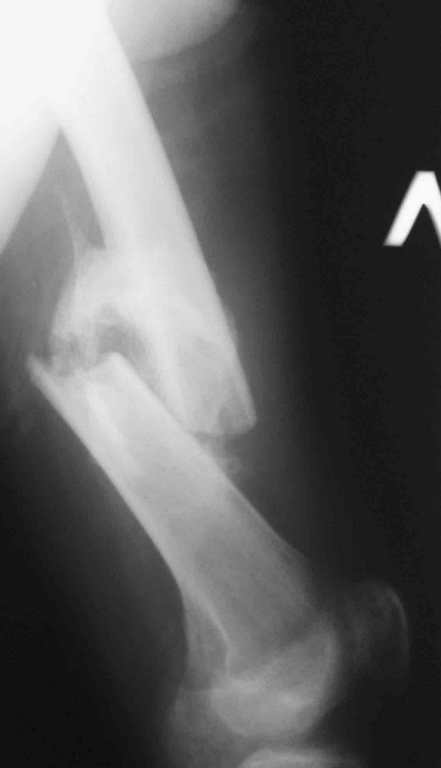

Иллюстрации к сообщению

Уважаемый Антон.Исходя из Вашего материального положения!! и наличия хорошего, грубого омозоления, равности длины конечностей и судя по снимкам не очень выраженной антекурвации, но выраженной контрактуры коленных суставов: чтоб не упустить время разработки суставов и активизировать больного, необходимо справа удалить стержень, рассверлить канал и произвести ЗИМО более толстым неблокир. стержнем т.к. на этом уровне можно получить устойчивый остеосинтез, после чего активизировать и дозированная, упорная ЛФК, а дальше после восстановления функции ,время покажеть.

Cyдя по представленным рентгенограммам оба бедра консолидированы. Необходима активная разработка движений в коленных суставах. Хотелось бы увидеть фотоснимки больного ( нижних конечностей спереди и сбоку). Если стержень мешает разработке движений то его надо удалить.